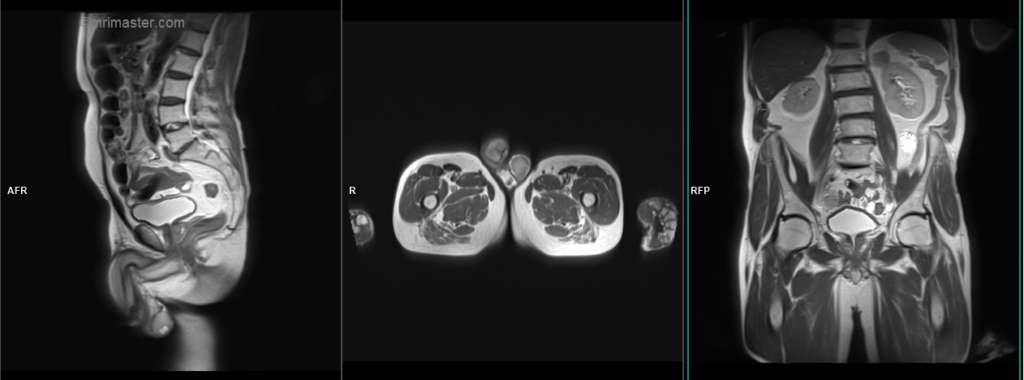

A three-plane HASTE localizer must be taken initially to localize and plan the sequences. These are fast single-shot localizers with under 25s acquisition time, which are excellent for localizing abdominal and pelvic structures. Take at least 3-4 slices in all planes to get the best results.

T2 stir coronal 5 mm big FOV

Plan the big FOV coronal slices on the sagittal plane, angling the positioning block vertically across the abdomen. Check the positioning block in the other two planes. An appropriate angle must be given in the axial plane (parallel to the right and left hip joint). The slices must be sufficient to cover the abdomen and pelvis from the anterior abdominal wall to the spinous process of the vertebrae.

The FOV must be sufficiently large to encompass the abdomen and pelvis from the kidneys down to the scrotum, typically ranging from 400mm to 420mm. Large FOV scans are essential for examining ectopic testis, as the testicles can be located anywhere along the gonadal vein. Therefore, it is crucial to cover the region from the kidneys down to the scrotum. Additionally, these scans are conducted to assess the para-aortic and pre-sacral nodes in testicular cancer imaging.